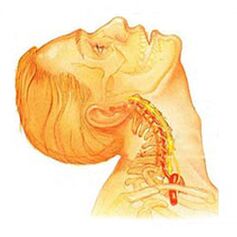

Durante o desenvolvimento da osteocondrose, as estruturas musculares e a maioria dos órgãos do corpo estão frequentemente envolvidos neste processo patológico. Isso se deve ao fato de que durante a infração máxima do feixe neurovascular, a circulação sanguínea e a motilidade dos músculos e órgãos são perturbados. Por exemplo, a osteocondrose mais comum é a osteocondrose cervical, que é acompanhada por dor na parte de trás da cabeça, náuseas, tonturas, deficiência visual e, frequentemente, zumbido. Esta doença tornou-se bastante "jovem": há um século, a osteocondrose era uma doença das pessoas em idade gerontológica e hoje os jovens também são susceptíveis a ela.

Osteocondrose da coluna cervicalapresenta sintomas locais e remotos de formas avançadas - com forte domínio da raiz, ou seja, contribui para o desenvolvimento de dor radicular intensa. Os sintomas de osteocondrose na coluna cervical são acompanhados por vários graus de disfunção, às vezes manifestada por uma limitação súbita da mobilidade da coluna cervical e bloqueios funcionais. As dores de cabeça podem ser puxadas e paroxísticas por natureza, com irradiação para a região interescapular ou região do ombro. No período agudo, os pacientes são diagnosticados com crises de dor no pescoço, que impedem e restringem os movimentos da cabeça e pescoço. Além do desconforto intenso, a síndrome dolorosa pode ser acompanhada por tonturas, insônia, dor, perda de apetite, depressão, doenças dos olhos e da faringe.